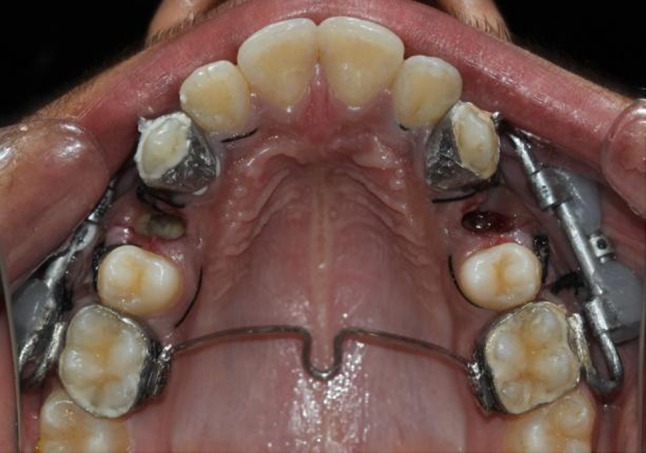

After the surgical procedure a custom-made intraoral distraction device was fabricated from a HYRAX expander (11 mm) (Fig. 8) which was trimmed, ground, and polished (Fig. 9). After preparation of the distractor screw, it was adapted on to the patient’s dental cast and soldering was completed on to the bands of the first molars and the canines that had been previously transferred to a dental cast (Fig. 10). Prior to soldering, the distractor screw was opened an amount equal to the mesio-distal width of the premolar to be extracted. Now intraoral distractors were cemented (Figs. 11, 12) and distraction was started in the PLD side on the same day. Distraction on the DAD side was started after a latency period of 3 days. The distraction device was activated twice a day at a rate of 0.8 mm per day. After completion of the distraction process, records were taken which included impressions, OPG and IOPAs and changes recorded (Figs. 13, 14, 15, 16, 17, 18). The patient was subjected to Pulp Vitality test and fixed mechanotherapy was started subsequently.

Fig. 11.

Distractors cemented bilaterally

Fig. 12.

Cemented distractors from occlusal view